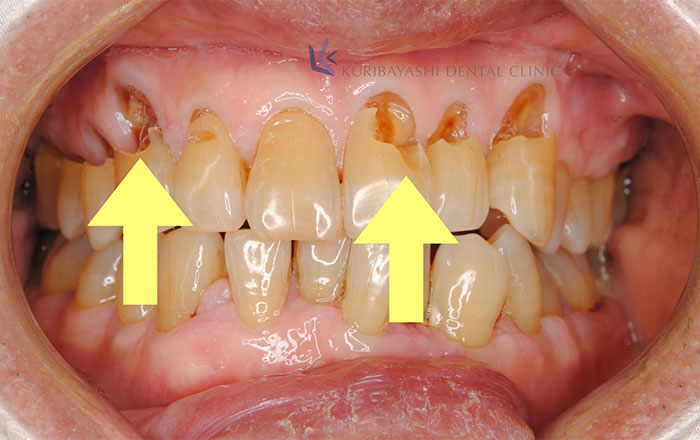

1)歯への悪影響

・歯の磨耗によって歯がしみる(知覚過敏)

・歯が欠ける・歯が割れて、噛むと痛い・噛み合わせが深くなり、被せ物が取れやすくなる

など、歯への悪影響として最終的に歯にヒビが入る、歯が欠ける、割れるといった症状があります。

2)骨への悪影響

・歯周病がより悪化しやすくなる・歯周病で既に骨が破壊されている人は、さらに進行する